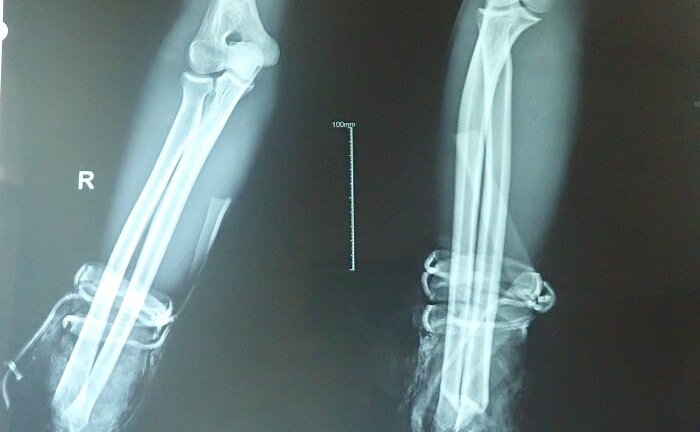

BVĐK Khánh Hòa (Nha Trang) đã nối thành công bàn tay bị đứt lìa khỏi cổ tay phải của một bệnh nhân nam 36 tuổi.